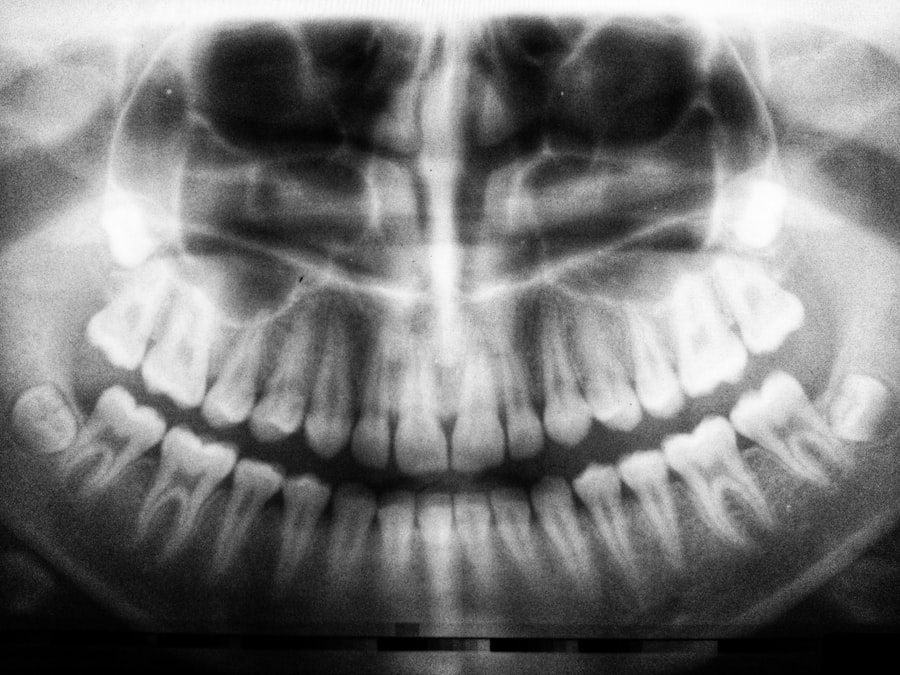

The Process of Cavity Formation

The formation of cavities is a multi-step process that begins with the demineralization of enamel. Initially, when acids produced by bacteria attack the enamel, it loses essential minerals like calcium and phosphate. This stage may not present any noticeable symptoms, but it marks the beginning of decay.

If you neglect proper oral hygiene during this phase, the enamel continues to weaken, leading to the formation of small holes or cavities. As the decay progresses deeper into the tooth structure, it can reach the dentin, which is softer than enamel and more susceptible to damage. At this point, you may start experiencing sensitivity to hot or cold foods and beverages.

If left untreated, the decay can penetrate further into the tooth, reaching the pulp where nerves and blood vessels reside. This stage can result in severe pain and may require more invasive treatments such as root canals or extractions. Understanding this progression emphasizes the importance of early intervention in preventing extensive damage.